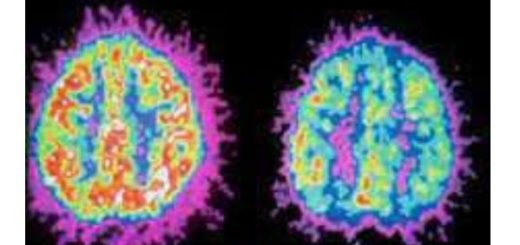

Glikasyon, şekerin/proteinlerin kontrolsüz birleşmesiyle ortaya çıkan ve dokularda yıpranmaya yol açabilen bir süreçtir.

Yüksek glisemik yük + kronik inflamasyon durumlarında:

protein yapıları bozulabilir,

damar/sinir dokusu etkilenebilir,

karaciğer ve safra sistemi daha “yapışkan/yoğun” metabolik atıklarla uğraşmak zorunda kalabilir.